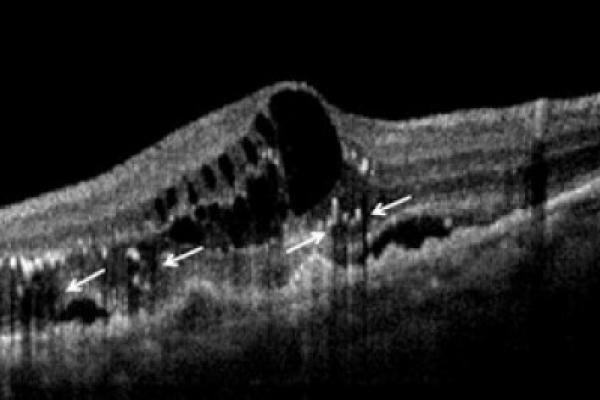

L’OCT ha rivoluzionato l’esame oculistico. Ogni oculista e ortottista deve capire le immagini OCT.

La tomografia ottica a radiazione coerente OCT è stata introdotta in clinica dal 1997, si è diffusa

rapidamente ed è diventata indispensabile, ha ampliato notevolmente le nostre conoscenze sulla

fisiopatologia e la clinica delle malattie retiniche e del glaucoma.

Questo corso, corredato da schemi facili da comprendere, permette di definire agevolmente le

caratteristiche dell’OCT.